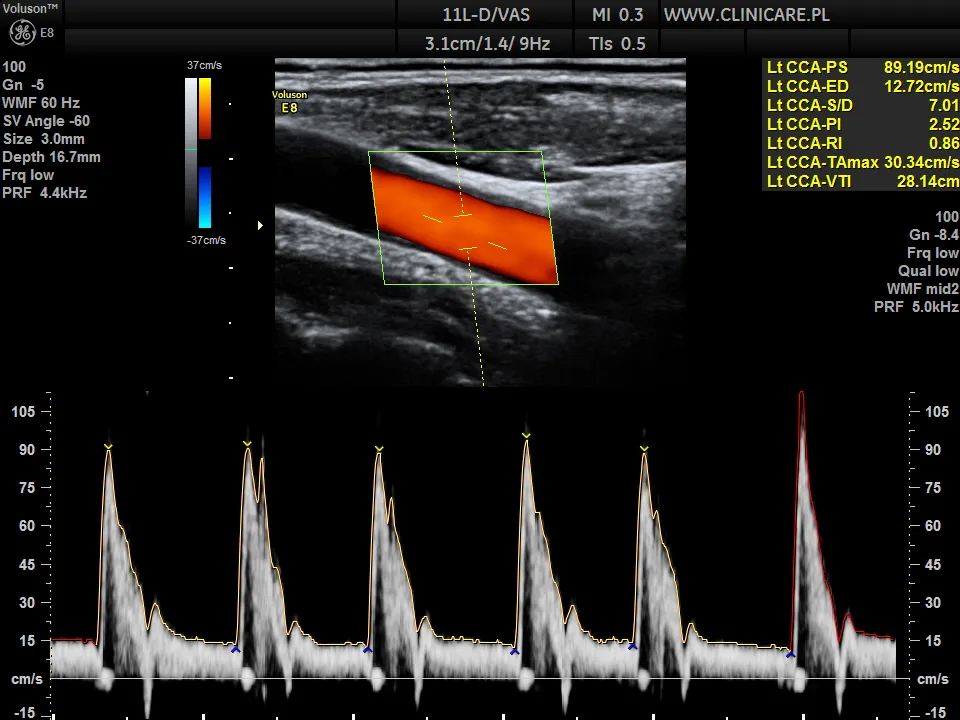

USG Doppler tętnic szyjnych: czy Twoje "magistrale" do mózgu są drożne?

USG Doppler tętnic szyjnych i kręgowych to kluczowe badanie, które pozwala mi ocenić stopień zwężenia tętnic doprowadzających krew do mózgu. Te zwężenia są często spowodowane blaszkami miażdżycowymi i mogą być bezpośrednią przyczyną udaru. Badanie jest absolutnie konieczne, jeśli podejrzewam miażdżycę w tych naczyniach. Jego wyniki są decydujące w kontekście ewentualnego leczenia zabiegowego, takiego jak endarterektomia (usunięcie blaszki) lub stentowanie (wszczepienie stentu poszerzającego naczynie), które mogą znacząco zmniejszyć ryzyko kolejnego udaru.